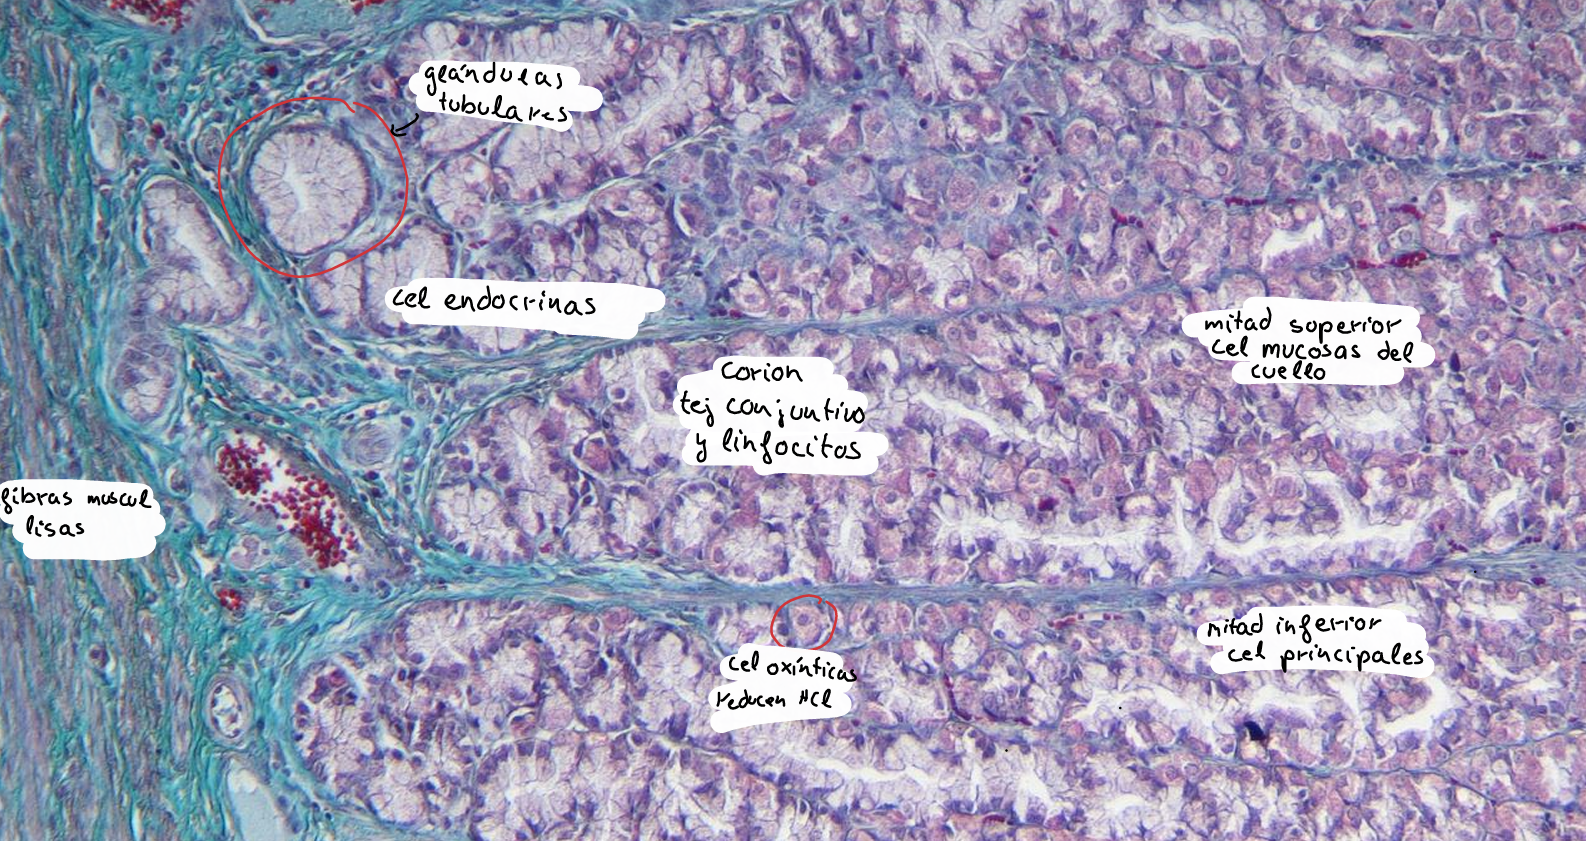

intestino grueso es la parte final del sistema digestivo, encargada de absorber agua y electrolitos, además de formar y eliminar las heces.

intestino grueso

colon